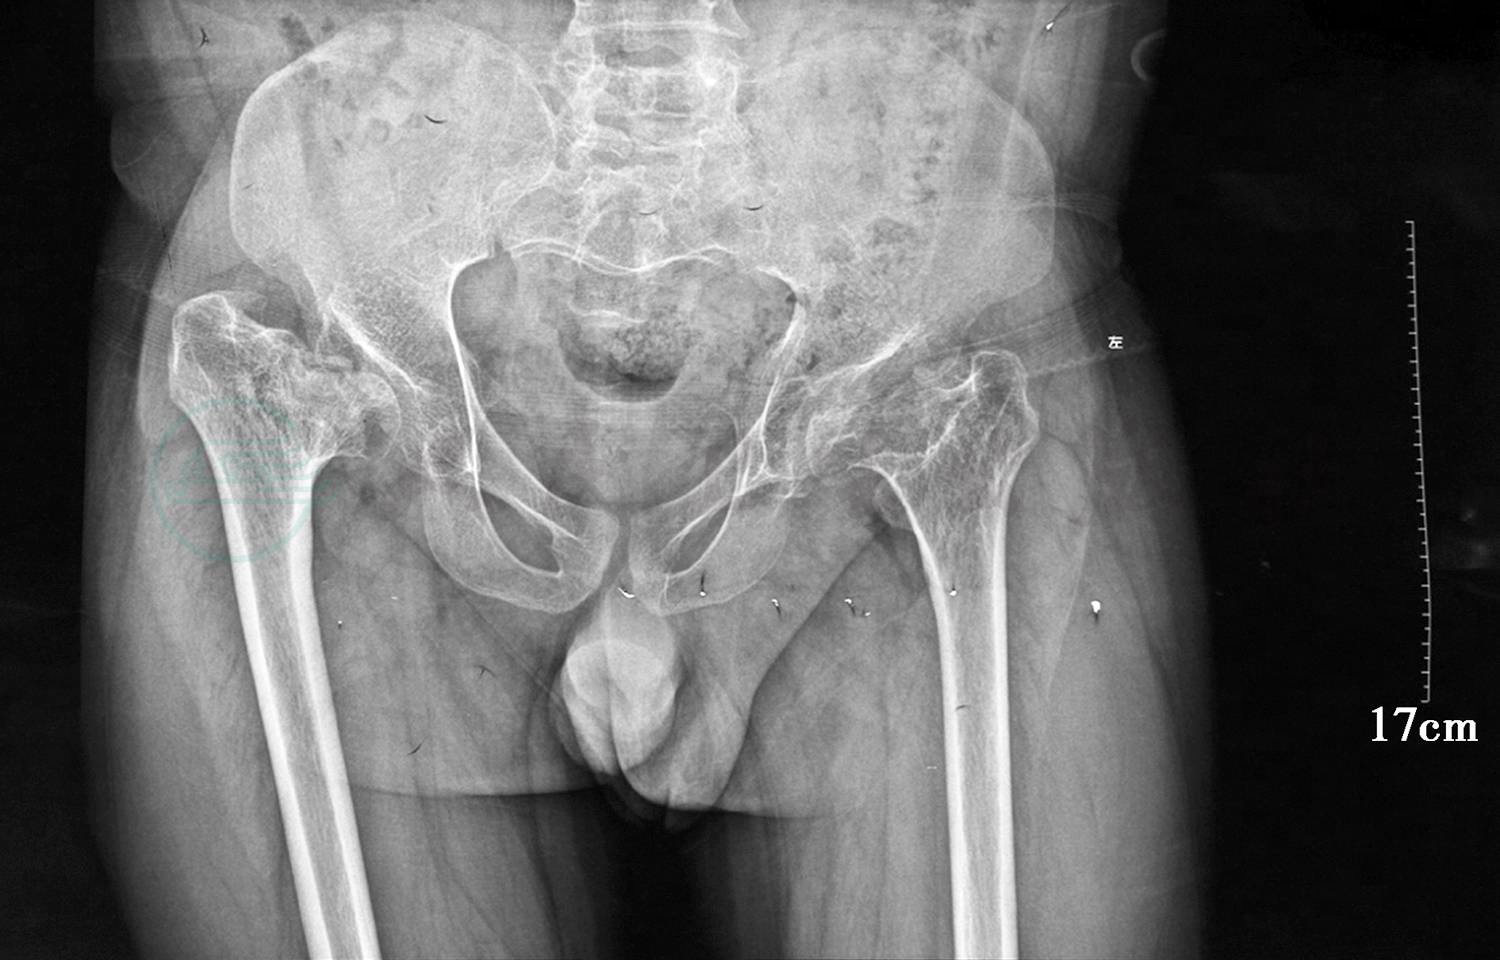

7.骨盆正位片(图4)双侧股骨头股骨颈塌陷吸收,右侧为甚。双侧髋臼变浅,髋关节面骨质毛糙,双侧股骨头外上移位。双侧髋关节骨质改变并半脱位。

图4 骨盆正位片